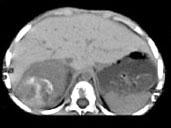

问题 男,5 岁,消瘦、贫血、纳差和腹部包块3个月,CT检查如图,下列说法正确的是 ( )

选项 A、该病灶来源于右肾上腺,考虑为神经母细胞瘤 B、该病灶来源于右肾,考虑为肾胚胎瘤 C、肿块密度不均匀,可见片状的较高密度,考虑为出血,也可见点状的钙化影 D、该病灶来源于肝脏,考虑为肝母细胞瘤 E、右侧腹腔内可见一巨大软组织肿块影,其边界欠清楚

答案 ACE